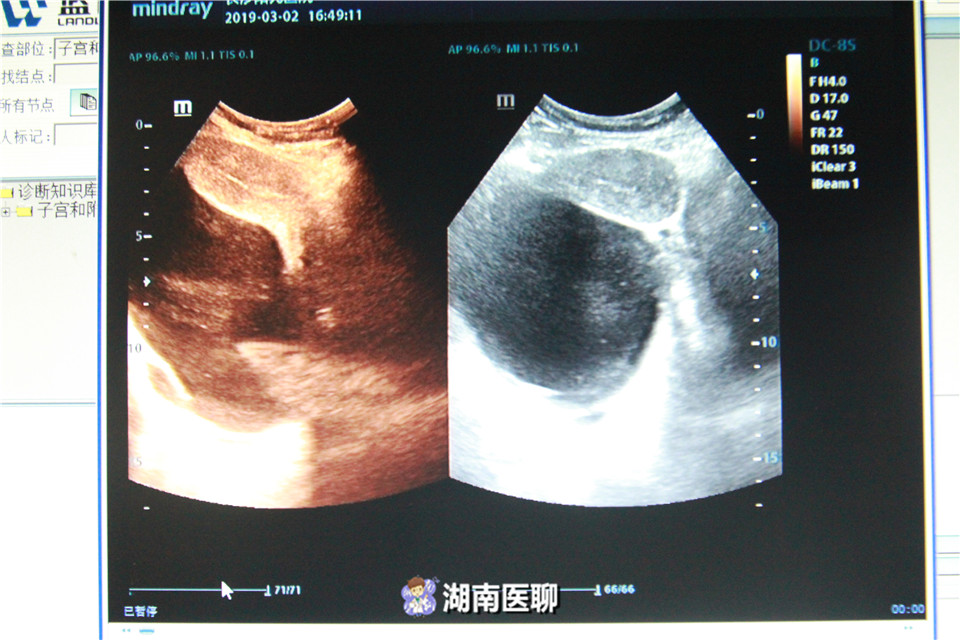

B超探查以及输卵管造影检查发现,刘女士右侧输卵管和卵巢系膜周边竟然有一个18厘米大的囊性包块,如足球般大小。

3月8日上午,医院为刘女士进行了宫腹腔镜手术,因包块生长位置特殊,手术进行了三个小时才结束。

通过最终病理化验,这个巨大的囊性包块确诊为卵巢浆液性囊腺瘤,是卵巢肿瘤的一种。